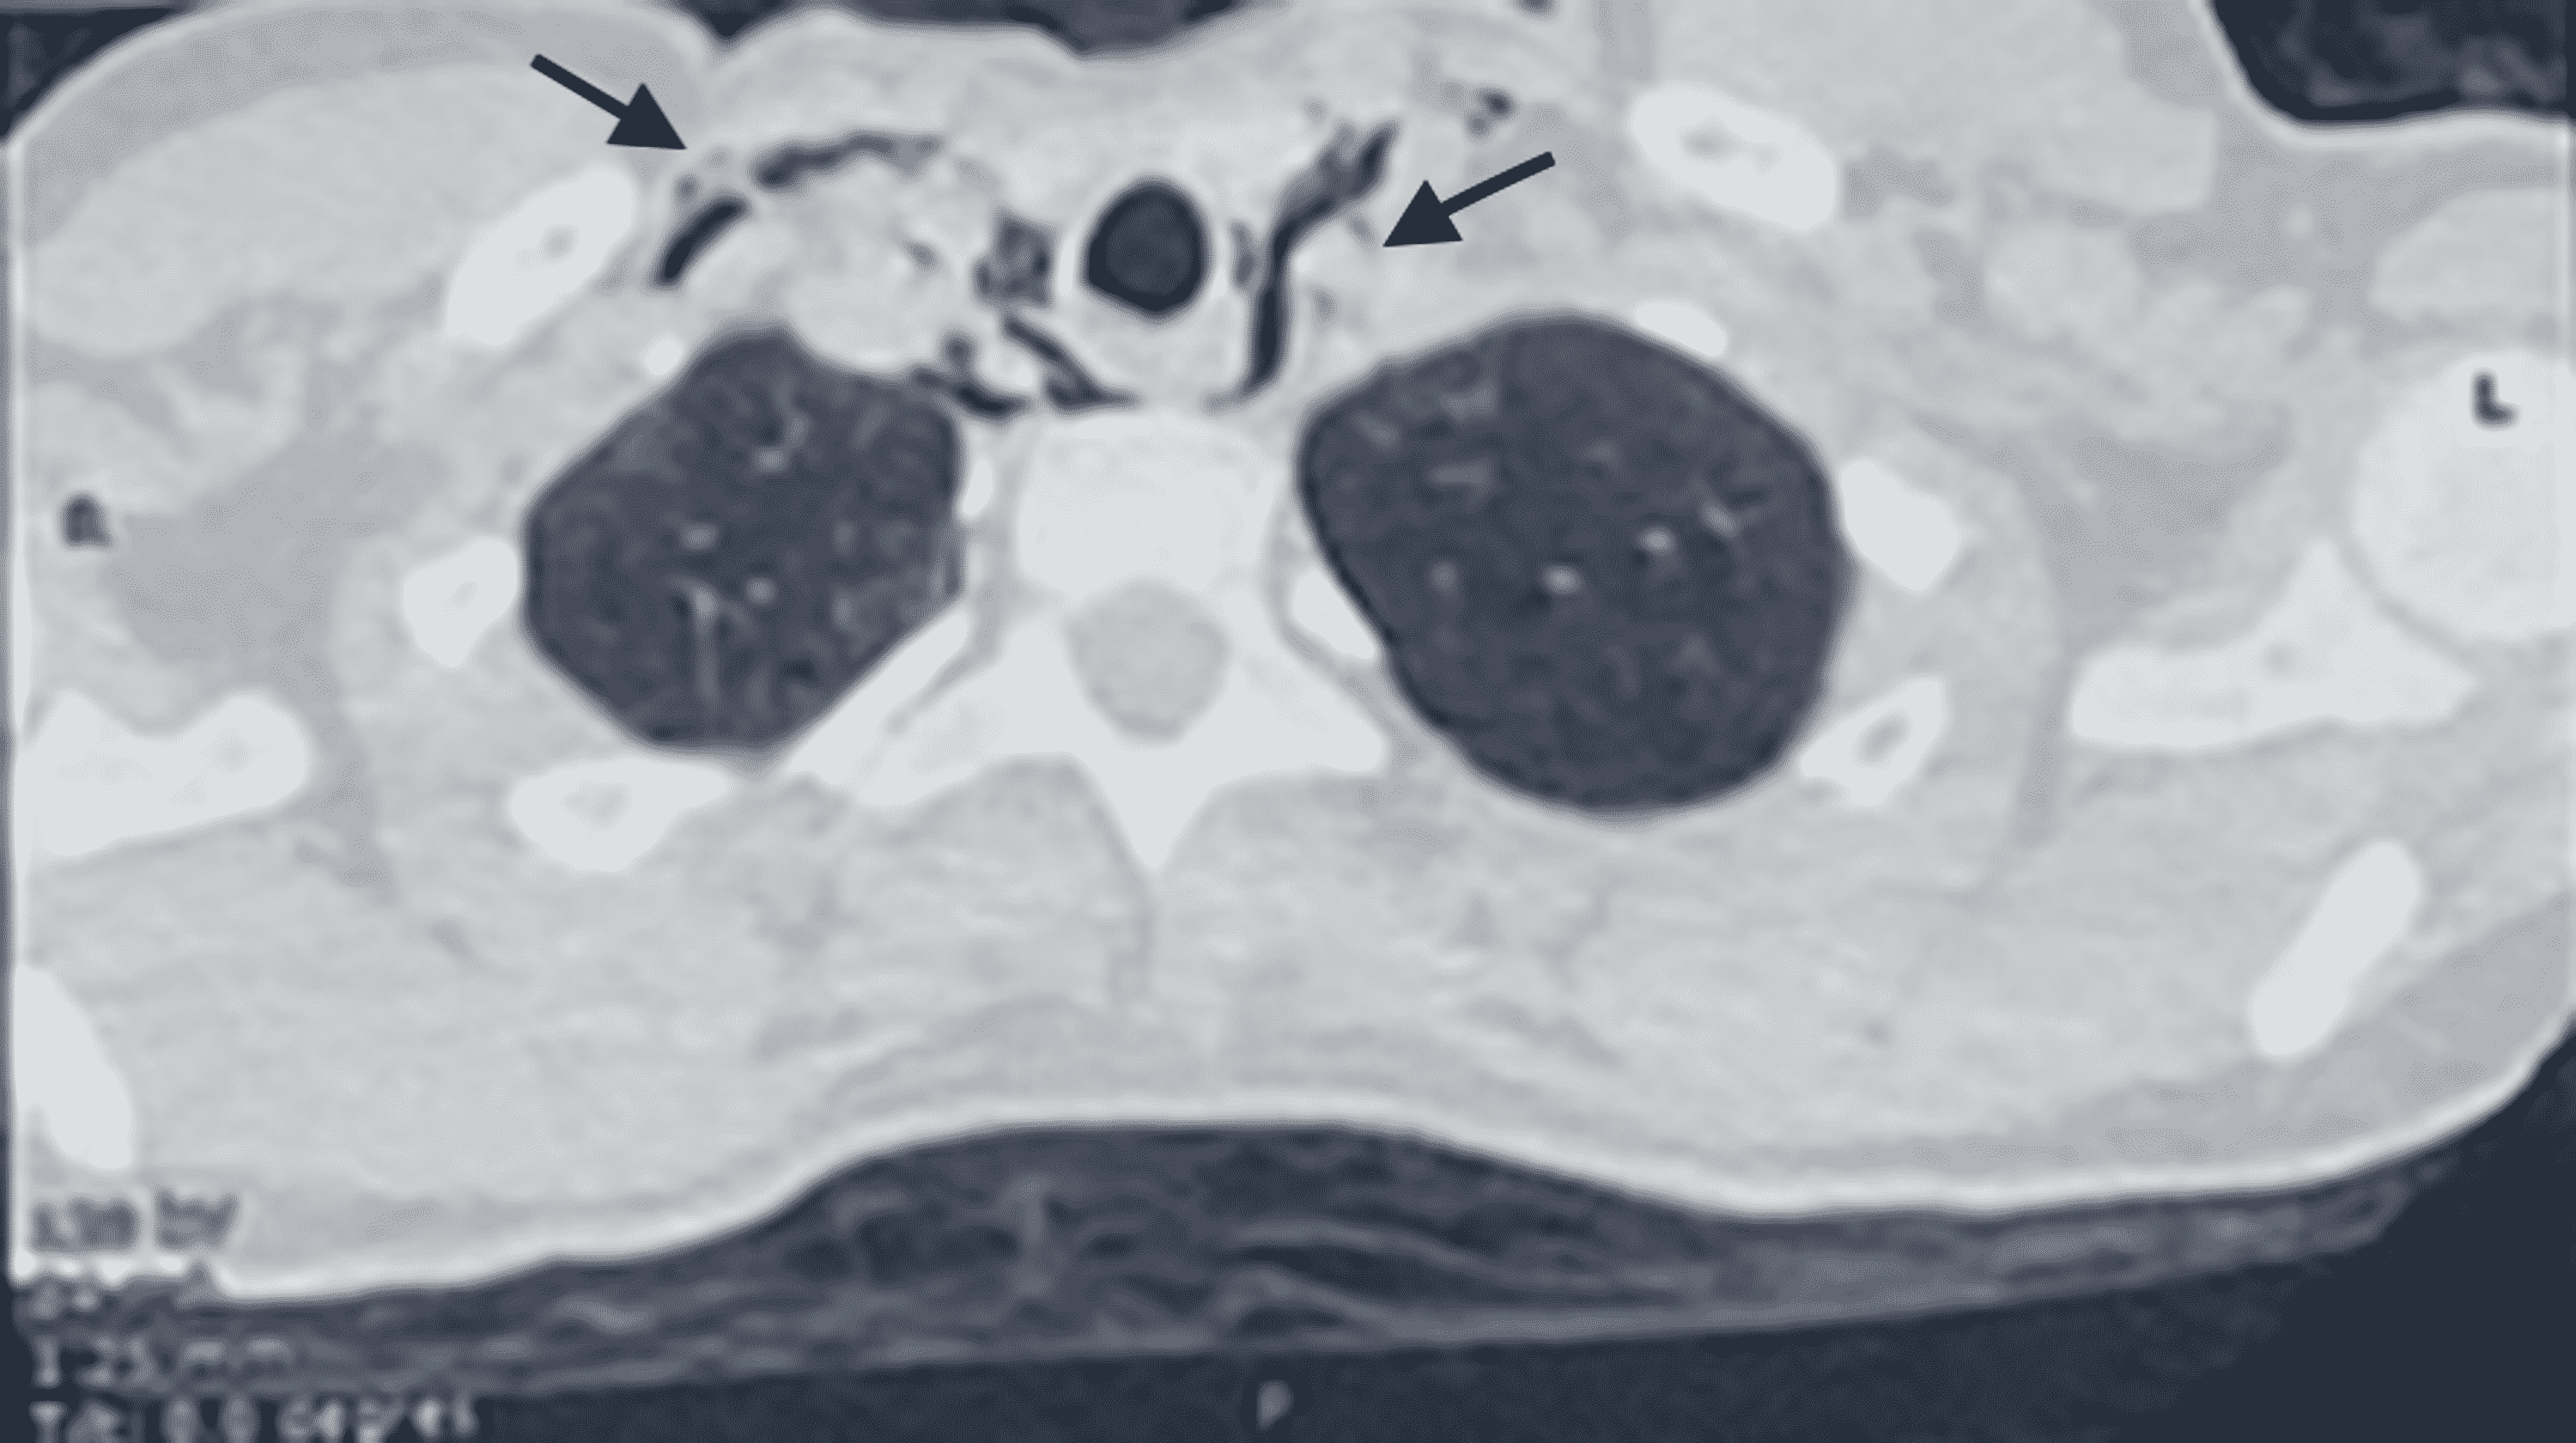

Macklin Effect . The macklin effect refers to pneumomediastinum caused by alveolar rupture and pulmonary interstitial emphysema tracking to the mediastinum along the peribronchovascular. Learn about the causes, clinical presentation, radiographic features and management of pneumomediastinum. Blunt traumatic alveolar ruptures, air dissection along bronchovascular. The macklin effect is a possible cause of pneumomediastinum in severe blunt chest trauma, involving air dissection along. The macklin effect is a rare but potentially serious complication of pneumomediastinum, caused by the. The macklin effect appears on thoracic computed tomography (ct) as linear collections of air contiguous to the. The aim of this review article is to describe the ct imaging spectrum of the.

The macklin effect appears on thoracic computed tomography (ct) as linear collections of air contiguous to the. Learn about the causes, clinical presentation, radiographic features and management of pneumomediastinum. The macklin effect is a rare but potentially serious complication of pneumomediastinum, caused by the. The macklin effect refers to pneumomediastinum caused by alveolar rupture and pulmonary interstitial emphysema tracking to the mediastinum along the peribronchovascular. Blunt traumatic alveolar ruptures, air dissection along bronchovascular. The macklin effect is a possible cause of pneumomediastinum in severe blunt chest trauma, involving air dissection along. The aim of this review article is to describe the ct imaging spectrum of the.

Macklin Effect The aim of this review article is to describe the ct imaging spectrum of the. Learn about the causes, clinical presentation, radiographic features and management of pneumomediastinum. The macklin effect refers to pneumomediastinum caused by alveolar rupture and pulmonary interstitial emphysema tracking to the mediastinum along the peribronchovascular. Blunt traumatic alveolar ruptures, air dissection along bronchovascular. The macklin effect is a possible cause of pneumomediastinum in severe blunt chest trauma, involving air dissection along. The macklin effect appears on thoracic computed tomography (ct) as linear collections of air contiguous to the. The aim of this review article is to describe the ct imaging spectrum of the. The macklin effect is a rare but potentially serious complication of pneumomediastinum, caused by the.